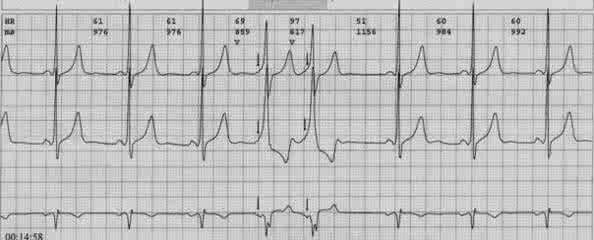

据了解,黄先生在5年前曾因阵发性心悸于深圳其他医院就诊过,诊断为“预激综合征,阵发性室上速”,但未予治疗,在院心电图也的确提示黄先生患有A型预激综合征。预激综合征是什么呢?李海鹰主任指出预激综合征是指心房部分激动由正常房室传导系统以外的先天性附加通道(旁道)下传,使心室某一部分心肌预先激动(预激) ,导致以异常心电生理和(或)伴发多种快速型心律失常为特征的一种综合征。发生预激的解剖学基础是,在正常的房室传导组织以外,存在一些异常的心肌纤维组成的肌束,即旁道 。 简单点说就是,心脏里多了一条捷径,而这条捷径导致患者的心脏某一部分在正常的心脏跳动之前提前跳动了,从而导致心律失常的发生。而预激综合征伴房颤可引起室颤,从而导致心跳呼吸骤停。结合患者相关病史,考虑黄先生存在这种病因的可能,同时,患者心电图提有ST-T改变,心肌标记物明显升高,冠心病不能除外,也不能排除是否有遗传性的致心律失常性心肌病。病因究竟是哪一个,还需进一步冠脉造影及心电生理检查进一步排查。

李海鹰主任是全国电生理专家,在电生理方面有很深的造诣,在心律失常及冠心病的诊治有丰富的经验,电生理及冠脉造影均为微创检查,对正常人来说并不会造成什么影响,但黄先生基本情况差,全身多器官功能不全,他能承受得了这些微创检查吗?另一方面,患者病因未除,病情随时可能进一步恶化,诱发恶性心律失常,患者会有很大的生命危险。情况进击,李海鹰主任决定尽快择期为患者进行相关检查,为了保证患者安全,李主任请了院内多个相关科室的专家会诊,一起商讨治疗方案,提高患者的耐受能力,再三斟酌之后,最后李主任决定先行电生理检查,尽可能帮助患者找到预激的“旁道”并关掉这条“旁道”,再行冠脉造影检查,但在这之前,还需要在密切关注下调整患者的身体状况,尽可能的恢复各脏器的功能。一切准备就绪,李主任带领团队于3月10日为患者行心内电生理检查,成功找到“旁道”,并予射频消融消除旁道,重复刺激,未见预激波,表明患者的预激“旁道”被李主任成功消除了!手术取得成功,黄先生亦无特殊不适,安返病房。